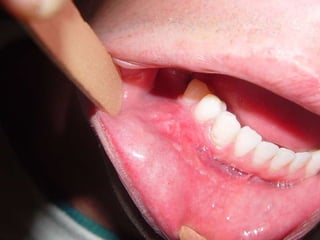

Granuloma Piogênico Lesão Nodular Séssil ou pediculada Avermelhada ou vinhosa Sangramento espontâneo e áreas de micro-ulceração superficial

Granuloma Piogênico Lesões nodulares de coloração avermelhada ou vinhosa Provavelmente uma reação inflamatória exagerada ao trauma menor Crescimento rápido, às vezes sangramento espontâneo Ocorre em qualquer idade mas parece mais freqüente em adultos jovens e adolescentes  Localização mais comum: gengiva (NEVILLE,2001)

Granuloma Piogênico Lesões mais antigas, são menos vasculares e mais fibrosas Papila interdental e regiões anteriores são áreas preferenciais, principalmente por vestibular (BORK,1996)

Granuloma Piogênico LesãoNodular Séssil ou pediculada Avermelhada ou vinhosa Sangramento espontâneo e áreas de micro-ulceração superficial

Granuloma Piogênico Lesõesnodulares de coloração avermelhada ou vinhosa Provavelmente uma reação inflamatória exagerada ao trauma menor Crescimento rápido, às vezes sangramento espontâneo Ocorre em qualquer idade mas parece mais freqüente em adultos jovens e adolescentes Localização mais comum: gengiva (NEVILLE,2001)

Granuloma Piogênico Lesõesmais antigas, são menos vasculares e mais fibrosas Papila interdental e regiões anteriores são áreas preferenciais, principalmente por vestibular (BORK,1996)